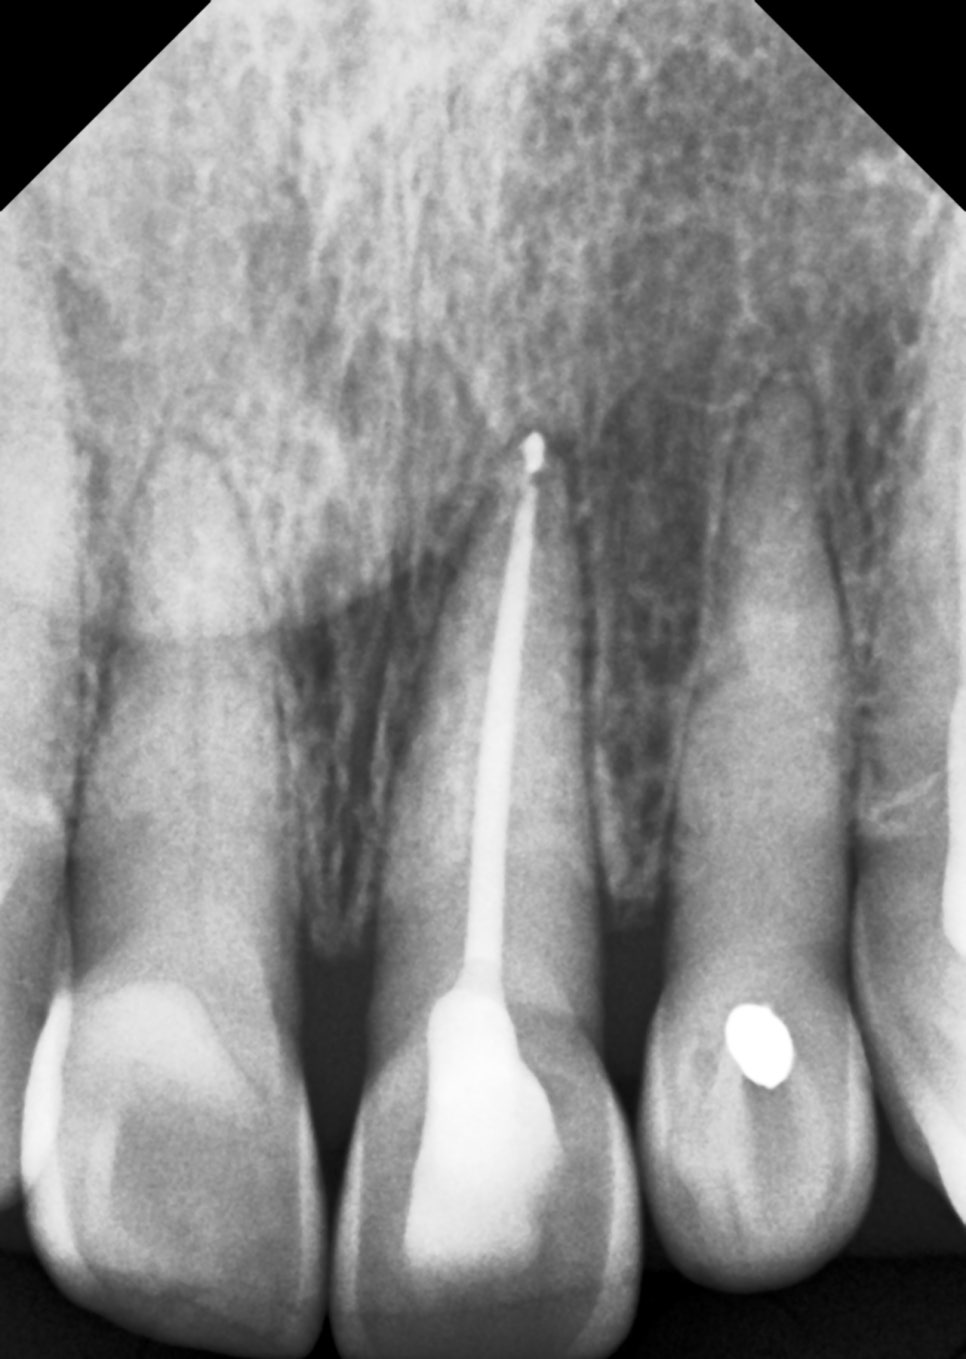

신경치료가 완료된 모습

신경치료는 통증을 없애기 위해 치아 내부의 신경뿐만 아니라 혈관(영양 공급원)까지 모두 제거하는 과정입니다.

영양분과 수분이 공급되지 않으면 치아는 퍼석퍼석한 고목나무처럼 변하는데요.

이 과정에서 치아의 상아질 구조가 점차 수분을 잃고, 유기물이 변성되면서 투명도를 잃고 어둡게 변하게 됩니다.

외상으로 신경이 서서히 죽는(괴사) 경우가 신경치료를 받은 경우보다 치아 색이 훨씬 더 어둡고 탁하게 변하는 경우가 많은데요.

치아에 강한 충격이 가해지면 치아 안쪽 신경관의 미세혈관이 터지며, 흘러나온 혈액이 치아 밖으로 배출되지 못하고 갇히게 돼요.

혈액 속의 철분(헤모글로빈) 성분이 치아 벽(상아질)의 미세한 구멍 속으로 스며들어 고착되며, 이것이 시간이 지나며 부패해 검붉거나 회색빛으로 비쳐 보이는 것이죠.

신경치료는 오염된 신경을 깔끔하게 제거하지만, 외상에 의한 괴사는 죽은 신경 조직이 치아 안에 그대로 남아 부패하게 되는데요.

이 과정에서 발생하는 가스와 부산물들이 치아 조직을 안쪽에서부터 오염시켜 신경치료를 한 치아보다 더 진한 변색을 유발하기도 합니다.

치아 안쪽에서부터 색이 어두워지는 것이기에 치아 내부부터 색상을 밝히는 실활치 미백이 필요하게 돼요.